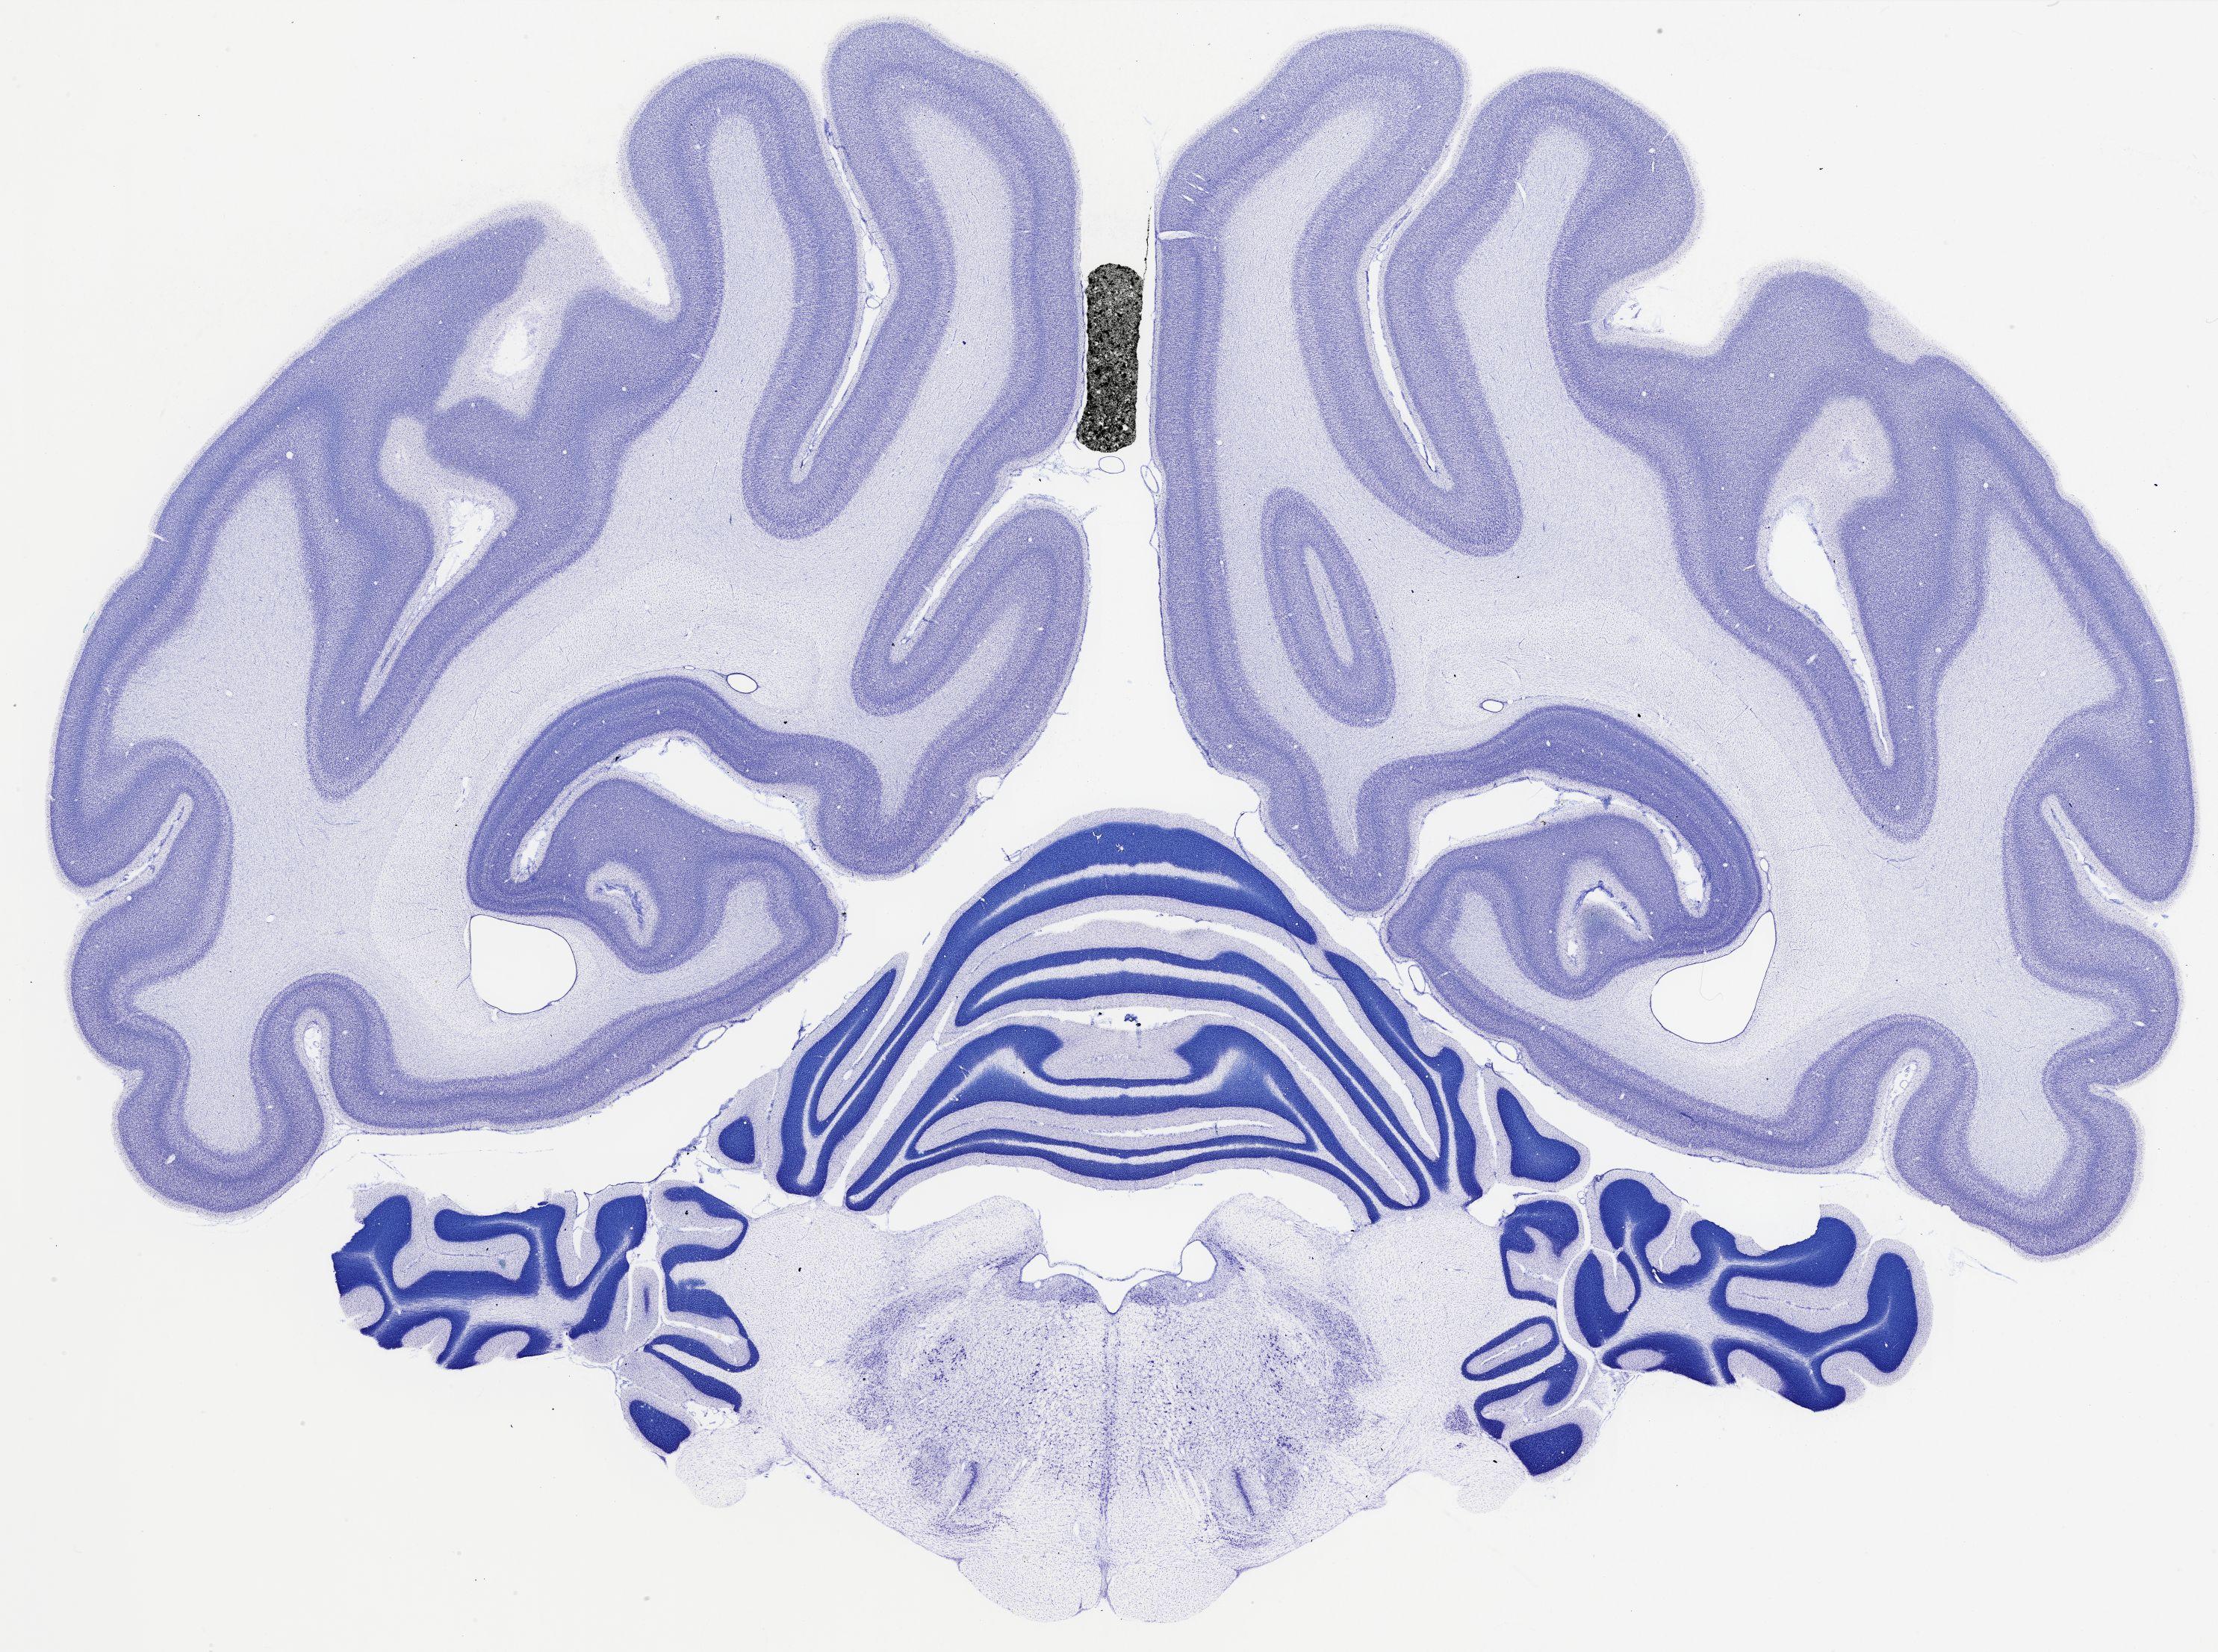

Datasets -> Chlorocebus Aethiops -> Nissl, coronal, histo, Whole-Brain, adult

[ Metadata ]   ·   Source: NeuroScience Associates

thumbnail

522